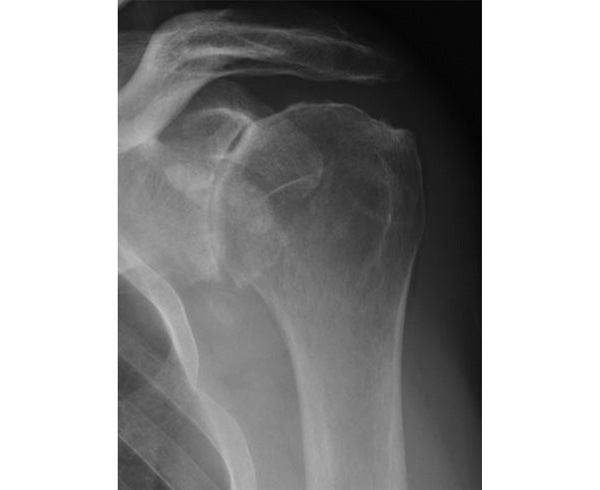

Glenohumeral Arthritis

Symptoms of GH joint arthritis include shoulder pain, stiffness, end range of motion pain (pain that worsens towards the end of your shoulder range), and pain at night. The pain is often described as a “deep ache” and becomes progressively worse over time. You may hear and feel a grinding sensation as you move your shoulder.